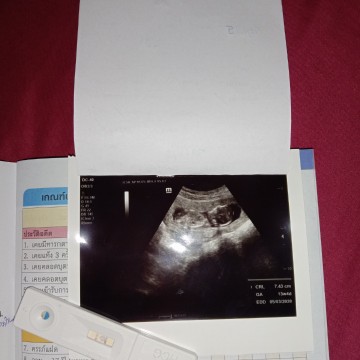

เมื่อวันที่2กันยายนที่ผ่านมา ไปซาวด์มา ในใบซาวด์ออกมาเป็น13w4d หมอบอก ท้องได้3เดือน1วัน ถูกต้องไหมค่ะ แล้วตอนนี้อายุครรภ์จะเท่าไรค่ะ ท้องแรก ไม่ค่อยรู้เรื่อง วีคค่ะ

1สัปดาห์=1วีค 4สัปดาห์=1เดือน 12สัปดาห์=3เดือนค่ะ 13สัปดาห์=3เดือน1สัปดาห์ค่ะ ในใบซาวด์อาจจะไม่ตรงกับที่หมอบอกค่ะเพราะในใบซาวด์อาจจะคำนวนว่าทารกอาจจะตัวใหญ่กว่าจำนวนครรภ์จริงค่ะ